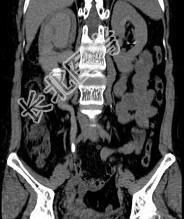

- 多项选择题患者女,44岁, 突发性胁腹部绞痛并向会阴部放射伴血尿一次。如图所示,下列说法正确的是 ( )

A、右侧肾盂肾盏扩张

B、右输尿管中上段扩张

C、右输尿管内可见沿输尿管走行的高密度影

D、右输尿管结石

E、左肾输尿管未见异常